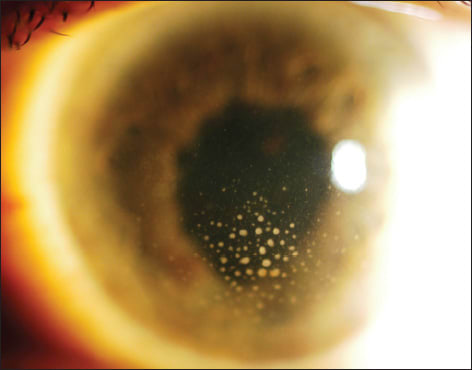

Figure 1. Most uveitis cases will benefit from immunosuppression prior to surgery. In cases such as this one of phacoantigenic uveitis, it is best to quiet the eye as much as possible before cataract extraction.